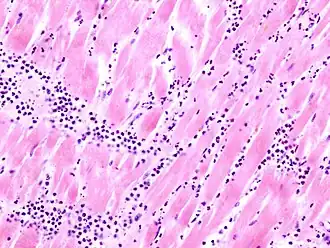

Martwica skrzepowa (łac. necrosis coagulativa) – martwica tkanek z ich następową kondensacją, utratą wody i utworzeniem skrzepu. Charakterystyczne dla tego typu martwicy są długo utrzymujące się kształty obumarłych komórek a raczej ich cienie w postaci kwasochłonnych kul lub pasm, w zależności od pierwotnego kształtu komórki. Koagulacja białek zachodzi w silnie zakwaszonej tkance, co hamuje aktywność lityczną enzymów. Taki obraz może się utrzymywać przez kilka dni, po czym pierwotnie sucha i martwa tkanka chłonie wodę, ulega fermentacji i uprzątnięciu przez leukocyty i makrofagi. Najczęstszą przyczyną jest niedokrwienie tkanek.

- martwica mięśnia sercowego,